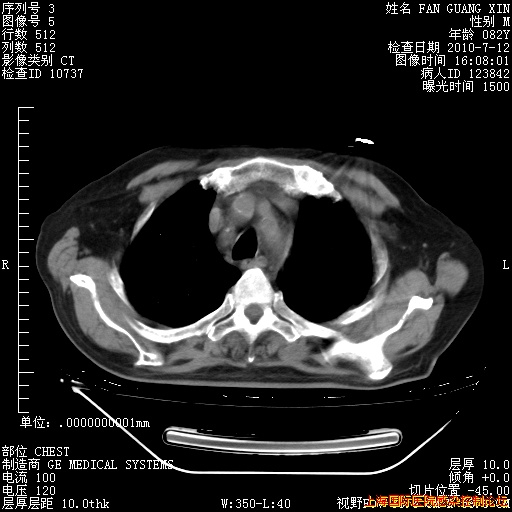

6月12日纵膈窗

回复

整整相隔30天的肺部CT好像有所好转啊。甲强龙减量第3天,需要观察体温。